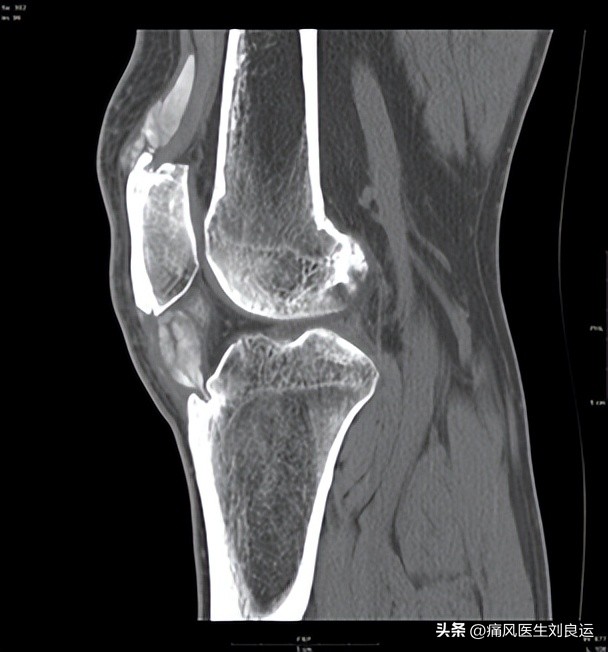

膝关节尿酸盐结晶沉积